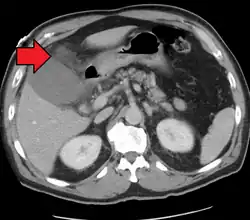

| Acute cholecystitis as seen on CT. Note the fat stranding around the enlarged gallbladder. | |

Acute cholecystitis with gallbladder wall thickening, a large gallstone, and a large gallbladder -